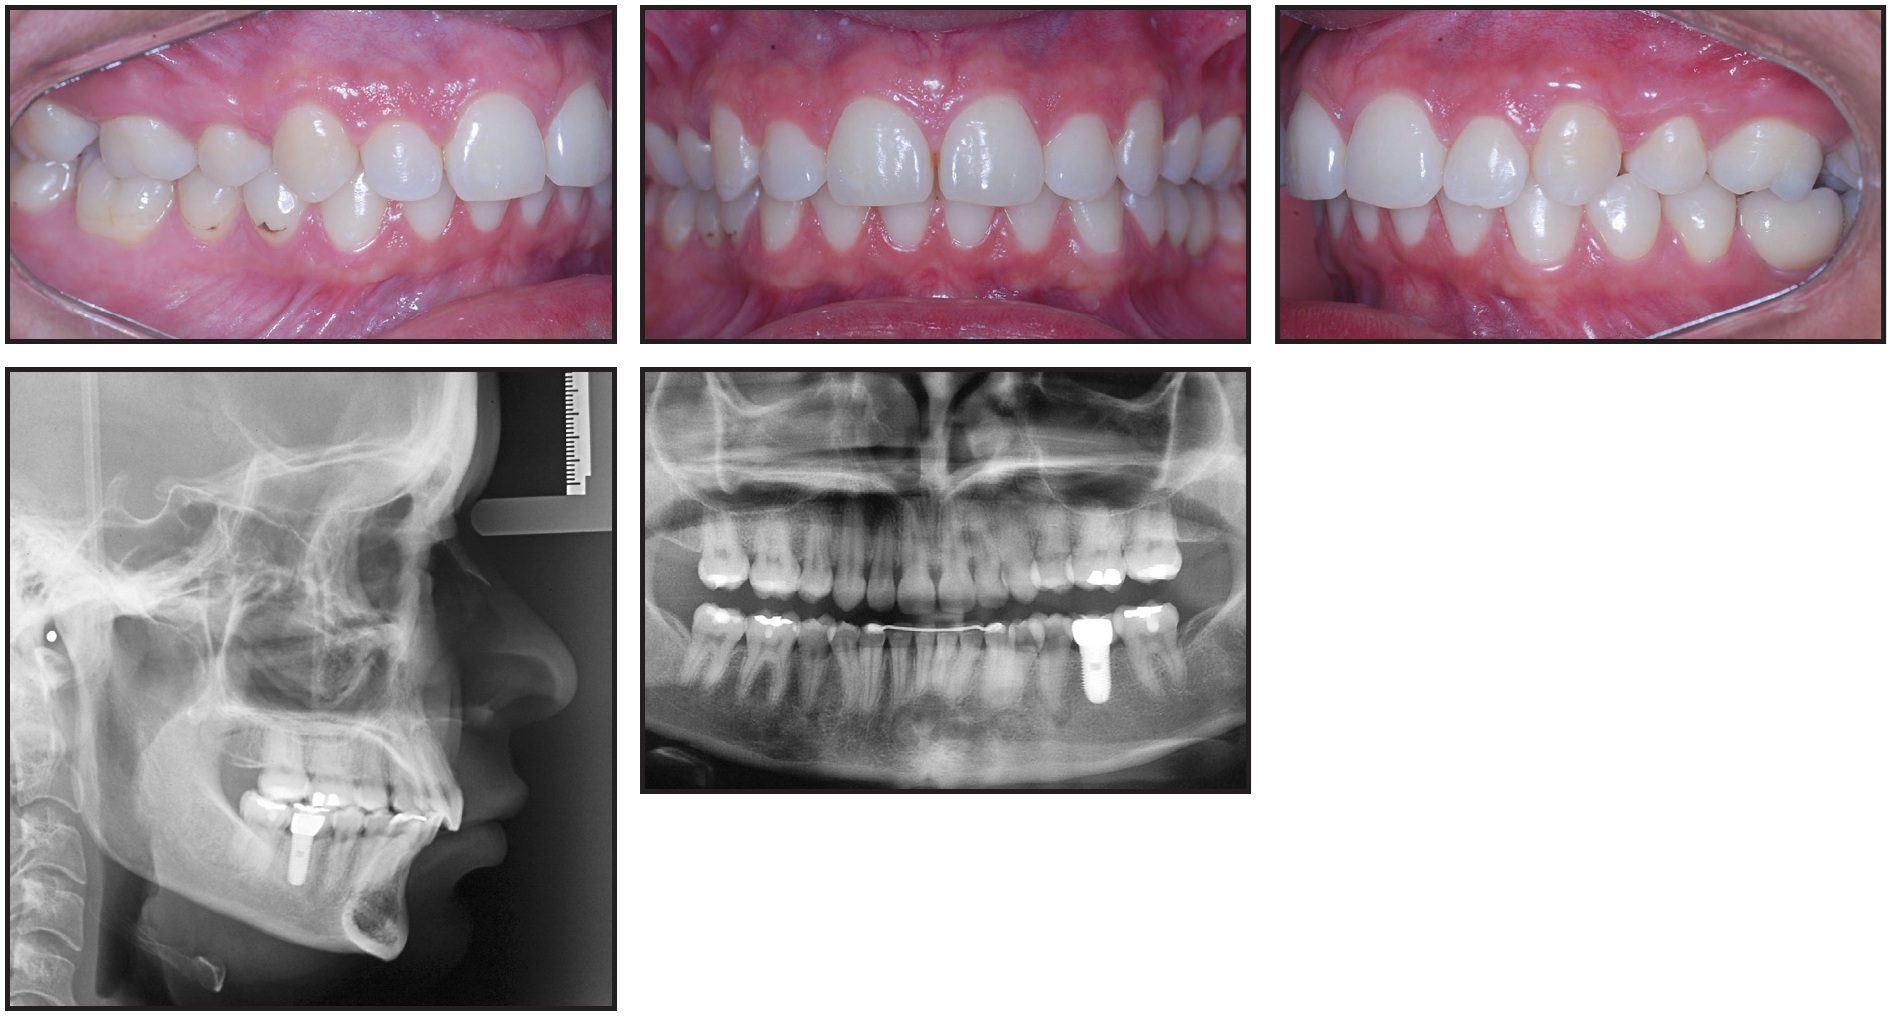

The clinical examination showed a symmetrical face, convex profile, incompetent lip seal at rest, and excessive maxillary incisor display upon smiling (Fig. 1).

Fig. 1 25-year-old female patient with Class II, division 1 malocclusion and deep bite before treatment (circle on panoramic radiograph indicates first molar extracted due to lesion in furcation).

The panoramic radiograph indicated adequate levels of alveolar bone and the presence of all teeth, including the third molars. (Because the lower left first molar had a lesion in the region of the furcation, it was extracted before the initial photographs were taken.) Cephalometric analysis confirmed the Class II malocclusion (ANB = 6o, Wits appraisal = +5mm), as well as brachyfacial characteristics (SNGoGn = 22º and FMA = 17º). Functional analysis showed that centric relation was coincident with centric occlusion; there were no signs of TMD.